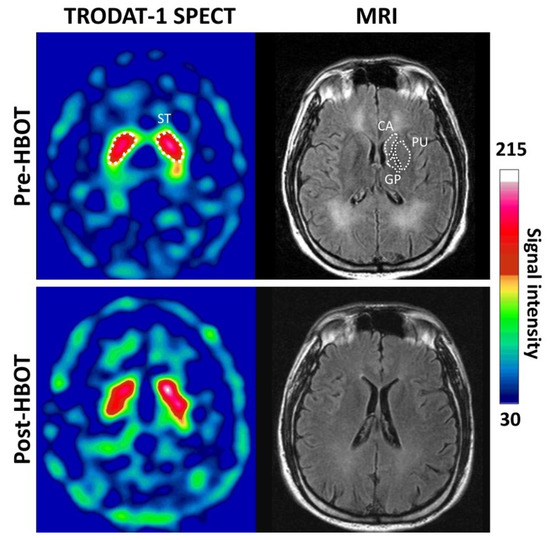

Figure 1 shows example SPECT images of the striatal region of a 35-year-old male subject obtained 3 h post-injection of 99mTc-TRODAT-1 and the MR images before and after HBOT. Besides globus pallidus lesions, T2-weighted FLAIR images showed extensive white matter hyperintensities on both side at baseline (pre-HBOT).

Figure 1. Representative transverse 99mTc-TRODAT-1 DAT SPECT and MR images. The striatal region of a 35-year-old male subject of 99mTc-TRODAT-1 and MR images obtained before and 3 months after HBOT. Regions of interest included the head of the caudate, the putamen and globus pallidus (white dot line) which correspond to 99mTc-TRODAT-1 SPECT. Relative 99mTc-TRODAT-1 DAT uptake in the striatal regions on both sides was low at baseline and slightly increased at 3-month follow-up.